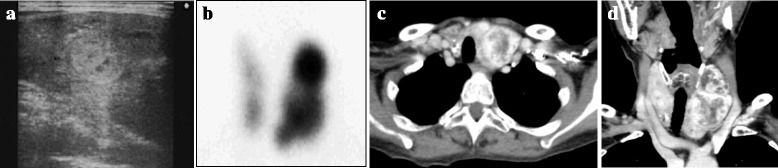

Fig. 2.

Imaging findings of the thyroid gland. Ultrasonography demonstrated multiple nodules in the thyroid gland (a). The thyroid nodules showed an increased uptake of 99mTc on thyroid scintigraphy (b). The axial (c) and coronal view (d) of the thyroid gland on contrast-enhanced computed tomography showed heterogeneously enhanced multiple tumors with microcalcifications